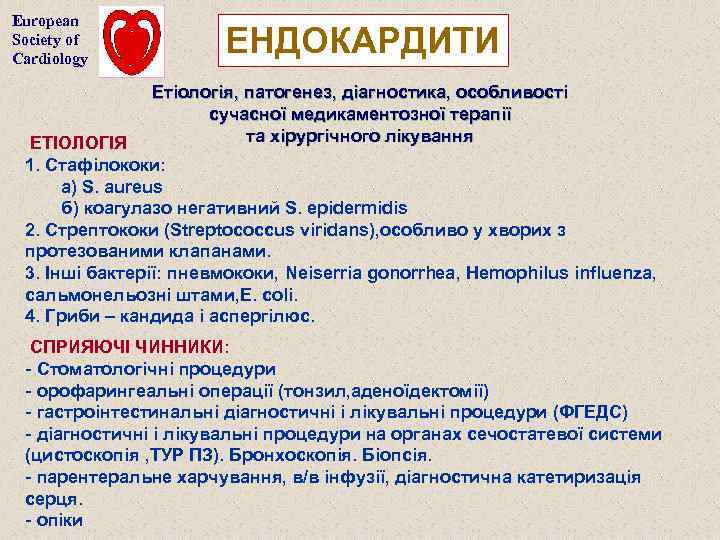

European Society of Cardiology ЕНДОКАРДИТИ Етіологія, патогенез, діагностика, особливості сучасної медикаментозної терапії та хірургічного лікування ЕТІОЛОГІЯ 1. Стафілококи: а) S. aureus б) коагулазо негативний S. epidermidis 2. Стрептококи (Streptococcus viridans), особливо у хворих з протезованими клапанами. 3. Інші бактерії: пневмококи, Neiserria gonorrhea, Hemophilus influenza, сальмонельозні штами, E. coli. 4. Гриби – кандида і аспергілюс. СПРИЯЮЧІ ЧИННИКИ: - Стоматологічні процедури - орофарингеальні операції (тонзил, аденоїдектомії) - гастроінтестинальні діагностичні і лікувальні процедури (ФГЕДС) - діагностичні і лікувальні процедури на органах сечостатевої системи (цистоскопія , ТУР ПЗ). Бронхоскопія. Біопсія. - парентеральне харчування, в/в інфузії, діагностична катетиризація серця. - опіки